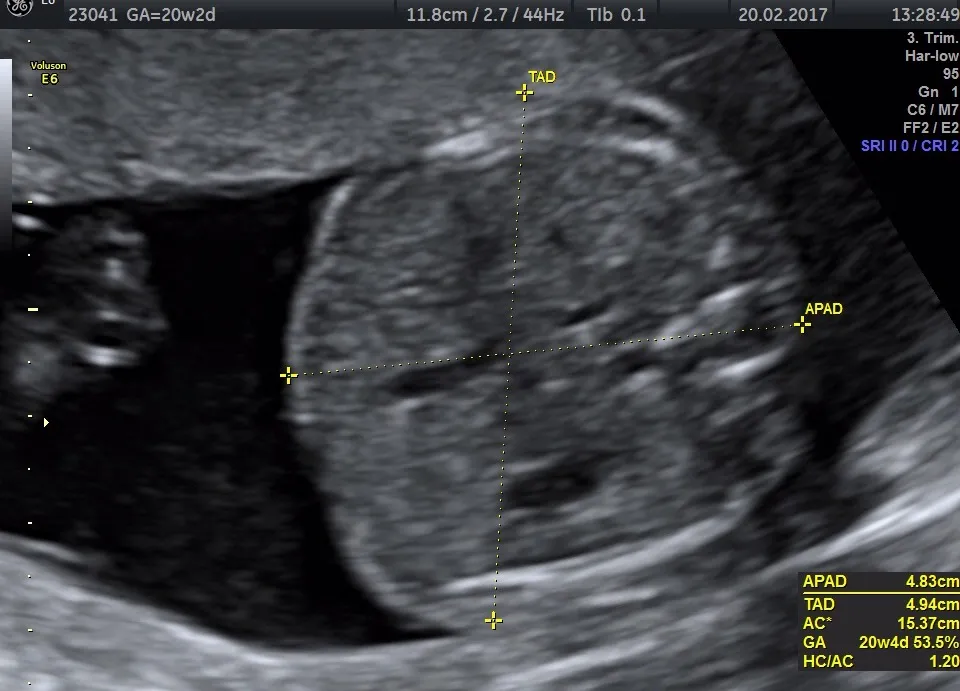

USG II trymestru, potocznie nazywane "połówkowym" lub "anatomicznym", to drugie obowiązkowe i refundowane przez NFZ badanie. Wykonujemy je między 18. a 22. tygodniem ciąży. To niezwykle ważny moment, ponieważ pozwala nam na bardzo szczegółową ocenę anatomii wszystkich narządów i układów płodu. Na tym etapie dziecko jest już wystarczająco duże, abyśmy mogli dokładnie przyjrzeć się jego rozwojowi i wykluczyć lub wykryć ewentualne wady wrodzone. Dla mnie, jako lekarza, to jedno z najbardziej fascynujących badań, dające pełny obraz rozwijającego się życia.Anatomiczna mapa twojego dziecka: co lekarz sprawdza od stóp do głów?

Podczas USG połówkowego mój wzrok skupia się na każdym detalu. Sprawdzamy dosłownie "od stóp do głów", aby upewnić się, że wszystkie narządy rozwijają się prawidłowo. Oto, co dokładnie oceniamy:

Jak rośnie moje dziecko? Ocena masy i rozwoju płodu

Głównym celem badania w III trymestrze jest ocena wzrastania płodu. Mierzymy poszczególne części ciała dziecka, aby upewnić się, że rozwija się ono w odpowiednim tempie. Wykluczamy w ten sposób hipotrofię, czyli zbyt wolne wzrastanie płodu, które może mieć wpływ na jego zdrowie. Na podstawie tych pomiarów określamy również przybliżoną masę płodu, co jest cenną informacją dla Ciebie i dla zespołu medycznego przygotowującego się do porodu.